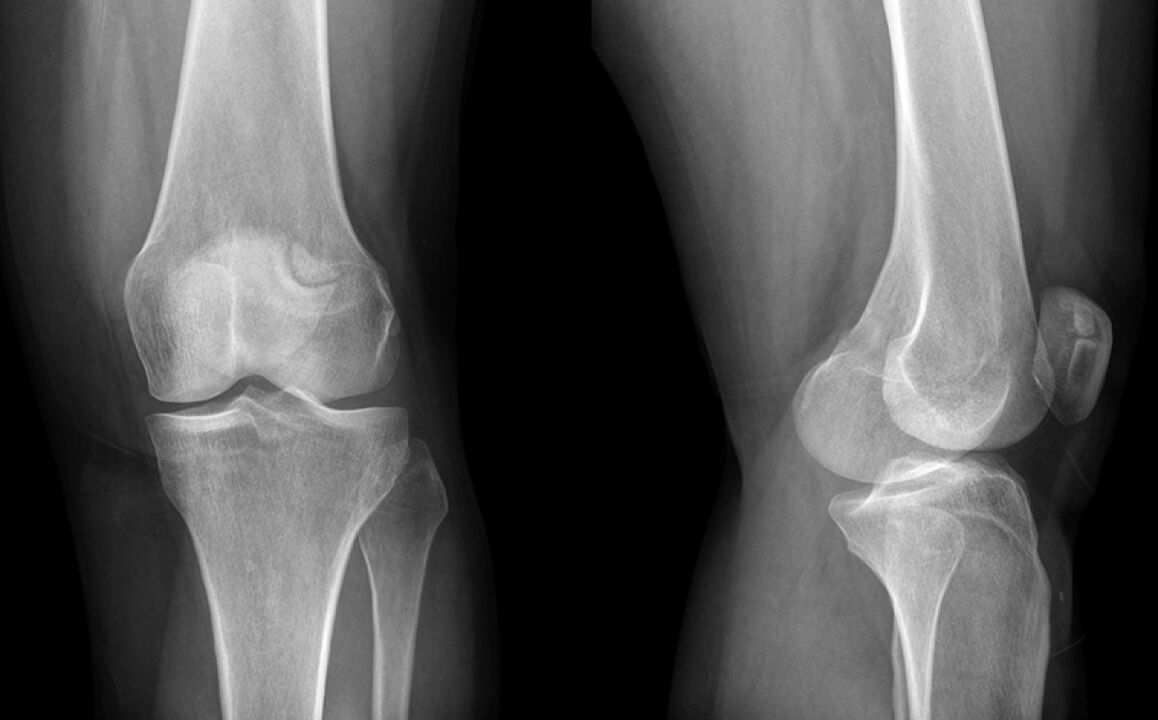

Das Knie verletzte drei Wochen. Am Ende ging ich zu einem Arzt, der den Schaden an den Meniskus vermutete und zu einem Röntgenaufbau geschickt wurde. Die Diagnose ist das Anfangsstadium der Arthrose des Kniegelenks.